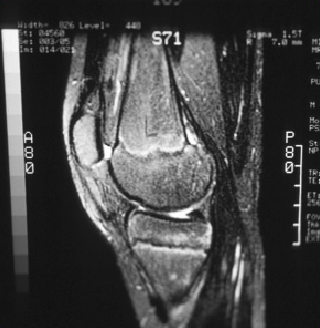

Sagittal magnetic resonance image (MRI) of the talus, showing an osteochondral lesion on the posterior aspect of the talar dome

Gupta RK, Kansay R, Aggarwal V, et al. Osteochondritis dessicans of the talus in a 26-year-old woman. BMJ Case Reports 2009; doi:10.1136/bcr.06.2008.0091